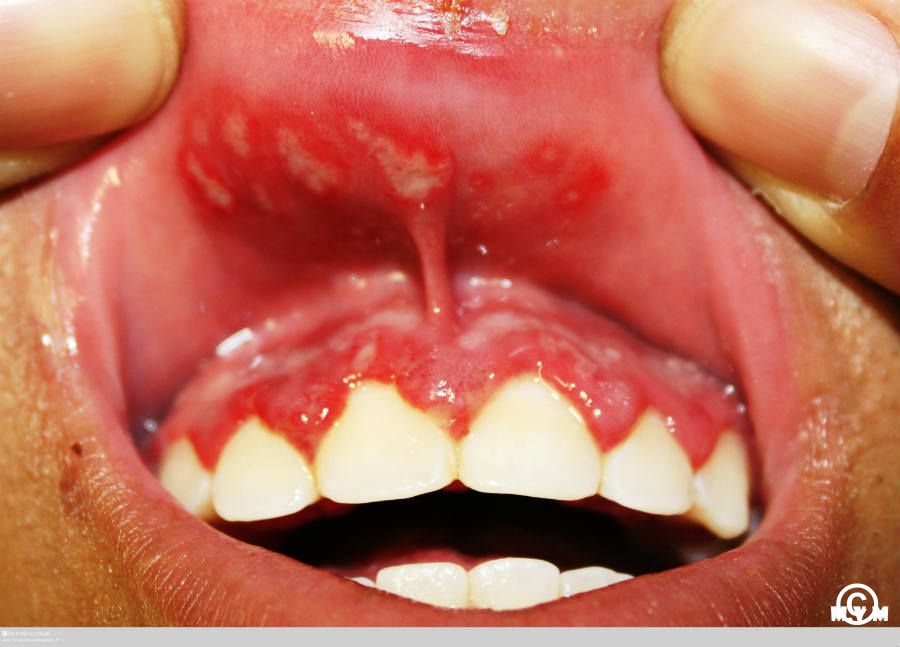

Figure 1 from An updated approach to chronic feline gingivitis

Figure 1 from An updated approach to chronic feline gingivitis Gingivitis Vs Stomatitis These conditions are often confused or assumed to be the same. Cats can be affected by inflammation of the entire mouth, called stomatitis or feline gingivostomatitis (fgs). The diseases however, are distinctly different, as we will see below. Managed through brushing, dental diets,. Gingivitis only affects the gingiva—or gumline—where the tooth meets the mucus membrane of the gums. By definition,. Gingivitis Vs Stomatitis.